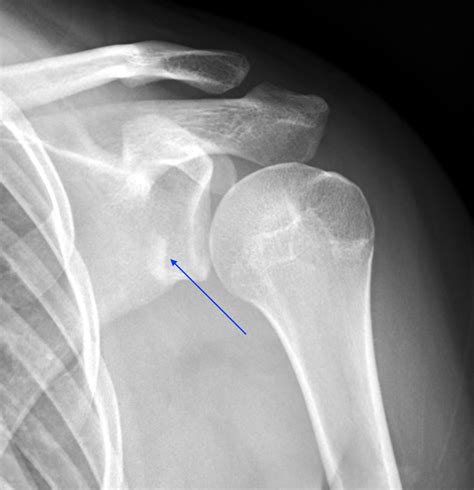

Hill-Sachs Lesion A small indentation or "dent" on the back of the humeral head, often caused by the bone hitting the rim of the socket during dislocation.

Bankart Lesion A tear or fracture of the labrum (cartilage) at the front of the glenoid socket.

The following table outlines common findings that may be noted on a Dislocated Shoulder X Ray report:

Finding Description